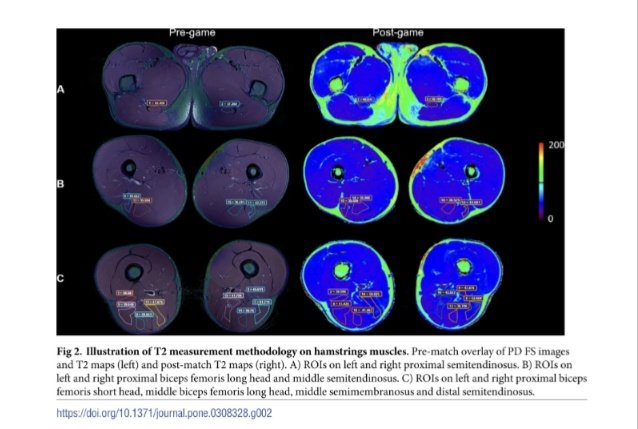

🆕 #AspetarTuesdayLecture 🎯Hamstring Muscle Function in Sprinting & Various Hamstring Exercises. 🗣️ By: András Hegyi 🔗Full Video👉 youtu.be/y-Yx4XnddMo?fe… 📢📢 Register now to attend in person or live sessions of Aspetar’s Tuesday Lecture Series 👉 bit.ly/3ZsySit